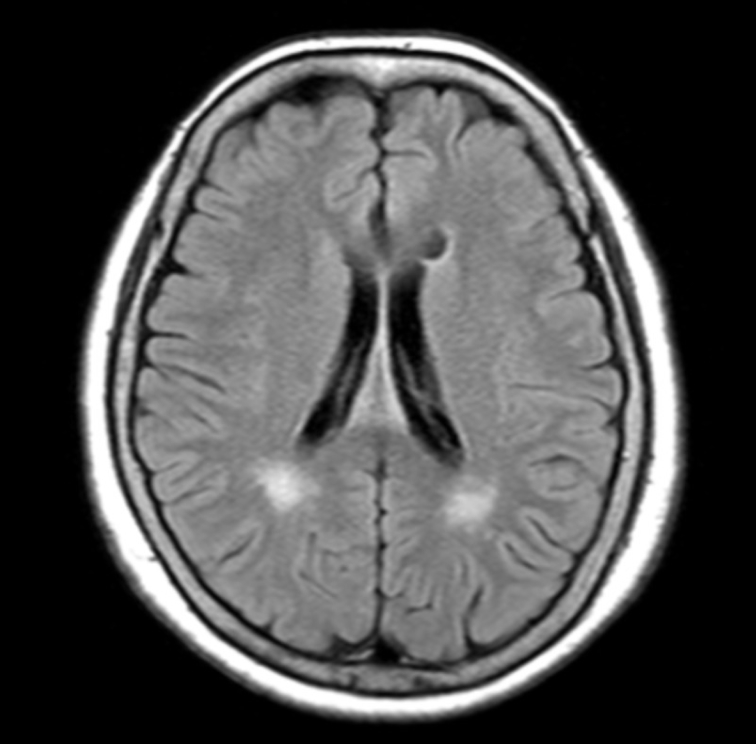

白質高信号領域の体積を自動計測

- 白質高信号領域の体積変化は様々な疾患の兆候になり得る

- 白質高信号領域(脳室周辺白質高信号領域・深部皮質下白質高信号領域)の体積の自動計測